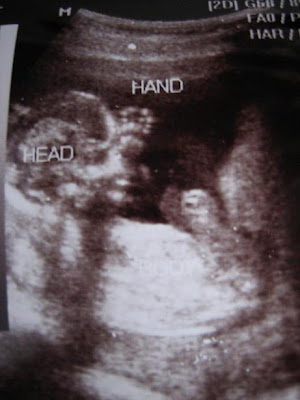

My baby's scan. Gynae said, "It's a teddy bear!" I beg to differ. That's obviously a kidney bean! 2.29cm in length. My dear hubby exclaimed excitedly, "Where where? I can't see!" That's how we got a blown up scan (with lower resolution >:[ I told my hubby not to talk at our next visit. I can't see clearly with this blurred scan). And all the terminologies of where is what on the scan.